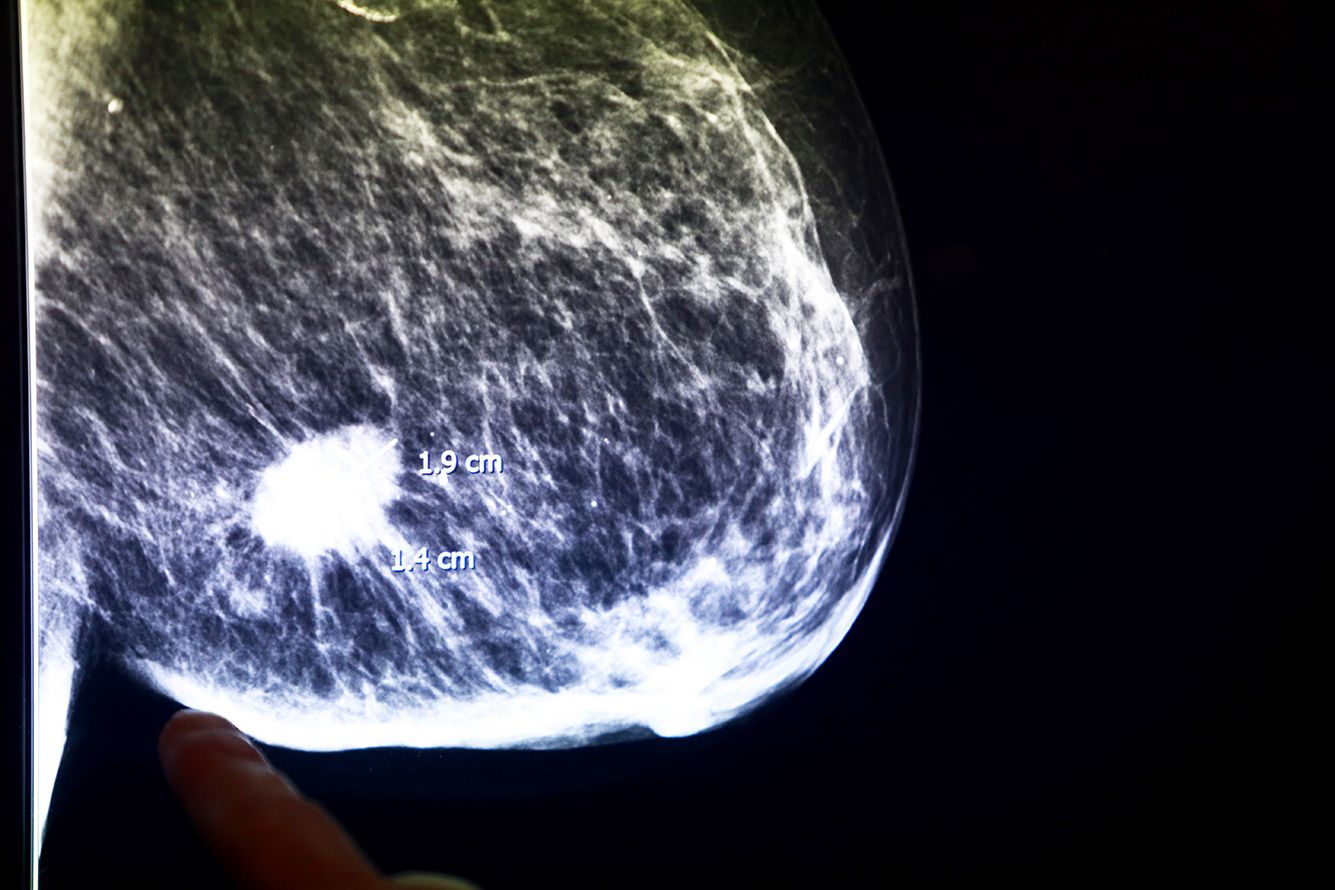

Выйдя из кабинета врача с онкологическим диагнозом, человек остается наедине со страхом и бесконечными направлениями на анализы. Зато потом, уже после победы над раком, люди с таким опытом могут помочь другим. Став равным консультантом, можно поддерживать новичков психологически, составить план действий, объяснить рекомендации врача или просто подсказать, где лучше выбрать парик после химиотерапии. Для женщин, которые столкнулись с диагнозом «рак молочной железы», такая поддержка особенно важна: часто им приходится привыкать жить без части своего тела. И опыт тех, уже прошел через это, для них очень ценен. О том, как в России работают равные консультанты в онкологии, рассказала руководитель направления обучения и оценки программы «Женское здоровье» Татьяна Голованова.